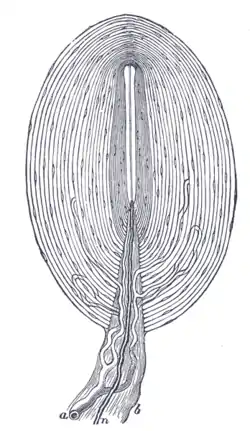

Pacinian corpuscle, with its system of capsules and central cavity. a. Arterial twig, ending in capillaries, which form loops in some of the intercapsular spaces, and one penetrates to the central capsule. b. The fibrous tissue of the stalk. n. Nerve tube advancing to the central capsule, there losing its white matter and stretching along the axis to the opposite end, where it ends by a tuberculated enlargement. | |

Pacinian corpuscle labeled at bottom | |

The Pacinian corpuscle is approximately oval-cylindrical-shaped and 1 mm in length. The entire corpuscle is wrapped by a layer of connective tissue. Its capsule consists of 20 to 60 concentric lamellae (hence the alternative lamellar corpuscle) including fibroblasts and fibrous connective tissue (mainly Type IV and Type II collagen network), separated by gelatinous material, more than 92% of which is water.[5] It presents a whorled pattern on micrographs.